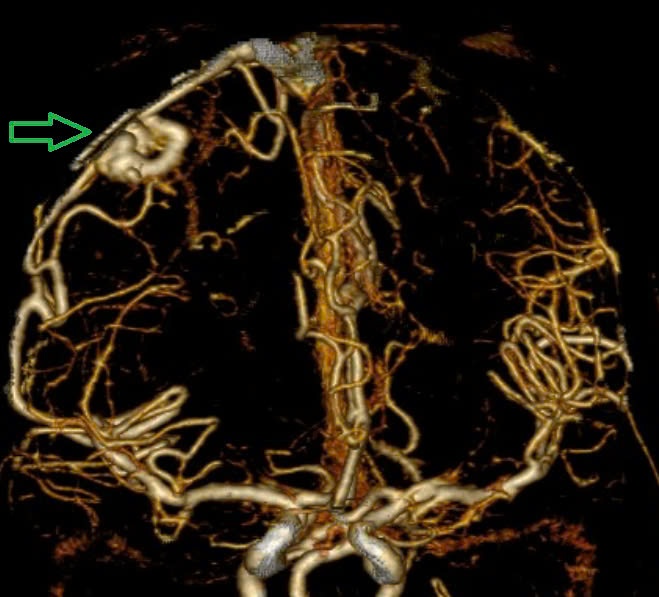

Hình ảnh chụp MSCT mạch não: Chảy máu não thuỳ đỉnh phải, chảy máu não thất do vỡ AVM ( điểm Spetzler Martin 2 điểm) của bệnh nhân. (Ảnh: BVBM CC)

Bệnh viện Bạch Mai cũng cho biết, mới đây tiếp nhận thêm một bệnh nhân 19 tuổi trong tình trạng co giật, hôn mê sâu, Glasgow 6 điểm, thở máy qua ống nội khí quản, liệt tứ chi. Qua khai thác tiền sử, trước đó, bệnh nhân chưa phát hiện bệnh lý gì.

Theo các bác sĩ tại Trung tâm Đột quỵ, kết quả chụp phim MSCT mạch não: Hình ảnh chảy máu não thùy đỉnh chẩm bên trái và não thất - phù não lan tỏa do vỡ ổ dị dạng AVM thuỳ đỉnh chẩm trái (điểm Spetzler-Martin 3 điểm). Sau đó, bệnh nhân đã được phẫu thuật hút khối máu tụ và lấy ổ dị dạng mạch não. Hiện tại, bệnh nhân vẫn đang điều trị tích cực tại khoa Hồi sức Ngoại, tiên lượng khả năng hồi phục hạn chế.